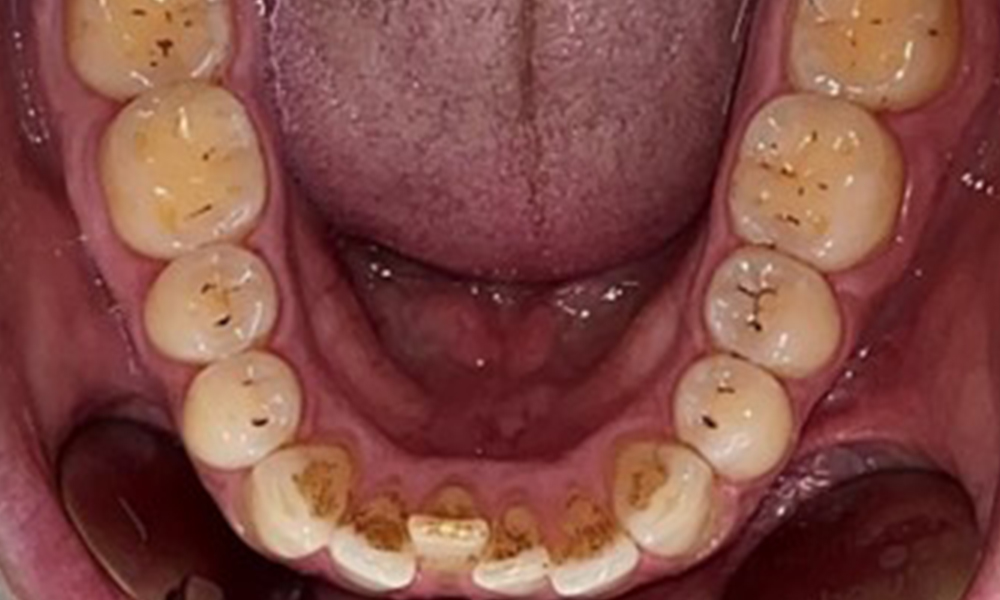

Vue occlusale de la mandibule.

Fig. 4: Vue occlusale de la mandibule, © Dr R. Krapf

Le patient a une dentition complète avec un total de 28 dents. Il y avait des érosions et des attritions notables. (Fig. 4, Fig. 5). En raison du bruxisme, le patient a porté pendant de nombreuses années une attelle avec une gouttière ajustée la nuit. Les érosions ont été causées par une consommation prolongée de boissons isotoniques. Aucune perte d'os parodontal ou carie active n'a été observée.